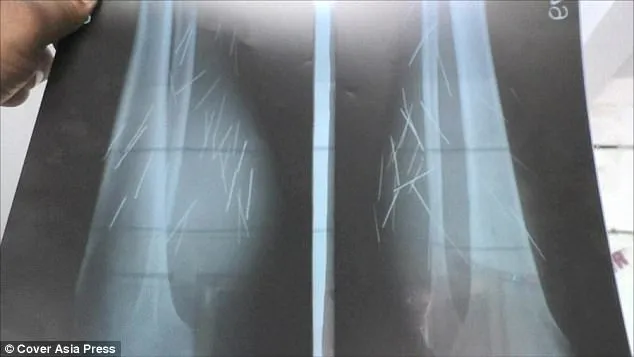

Karena tak tahan dengan rasa sakit yang dialaminya, Devi pun memutuskan untuk memeriksakan diri ke dokter. Setelah dilakukan X-ray, betapa terkejutnya dokter saat mendapati bahwa setidaknya ada 70 jarum dan paku yang bersarang di kakinya.

Selain itu, di kakinya terdapat banyak sayatan luka. Dokter pun dibuat bingung dengan kondisinya, karena dari pandangan medis, tak mungkin ada jarum dan paku tumbuh sendiri di kaki manusia.